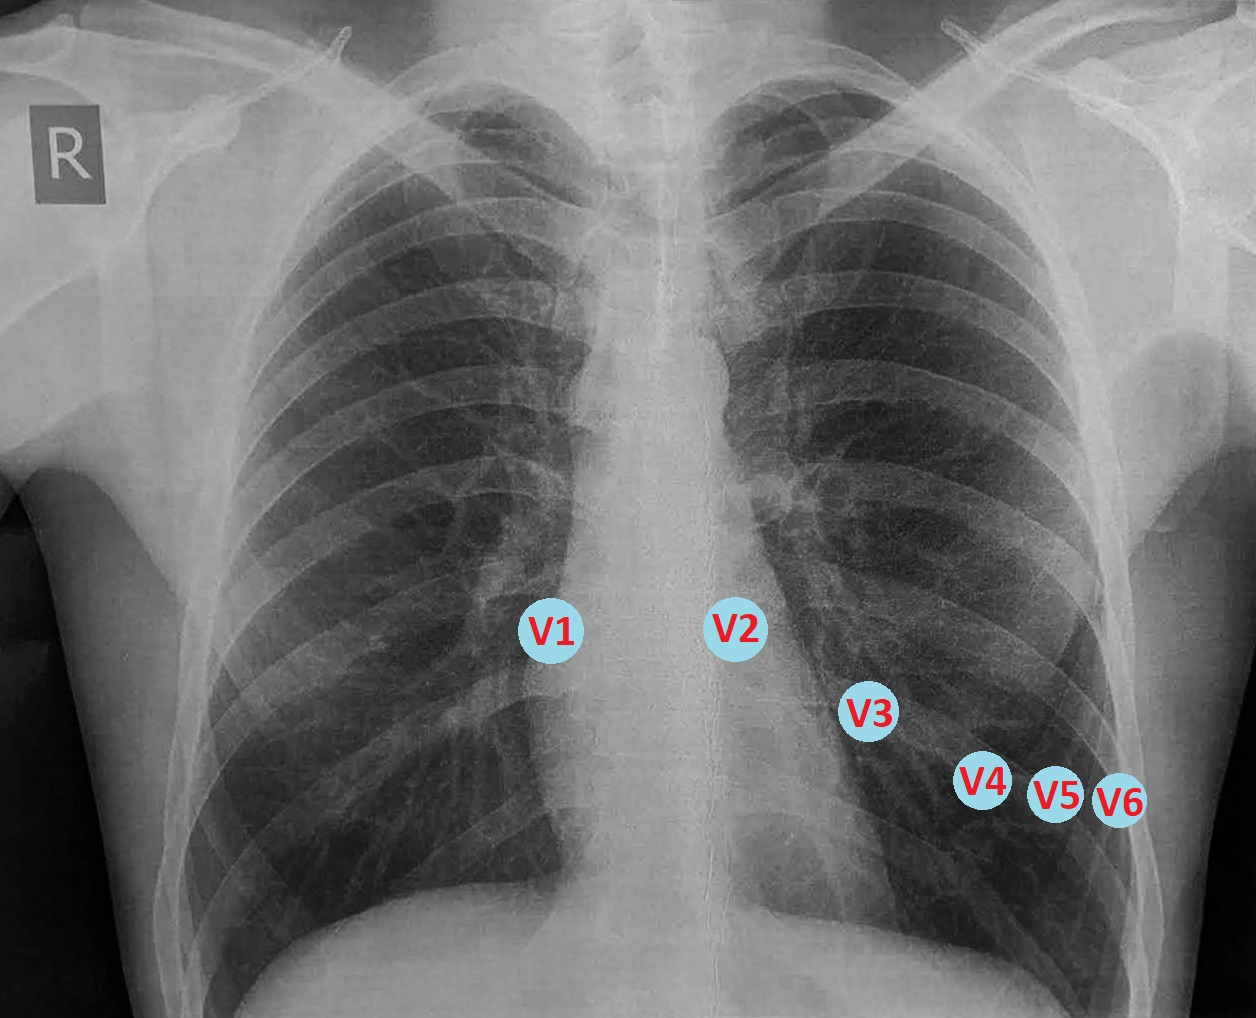

Чоловік 37 років, спортивної статури, доставлений ургентно каретою ШМД із скаргами на загальну слабкість і біль за грудиною середньої інтенсивності. Пульс 80 уд./хв., АТ=110/70 мм рт.ст.

За два дні до госпіталізації виконував інтенсивну фізичну роботу (перевантажував дуже важкий груз), після чого вперше відчув біль в лівому плечі, самостійно приймав НПЗП без значного ефекту. Упродовж двох днів стан погіршувався, - виникла значна слабкість, задишка, з'явився і посилився біль за грудиною. Самостійно звернувся до районної лікарні, де на ЕКГ було виявлено патологічні зміни і хворого ургентно транспортовано в спеціалізоване кардіологічне відділення.

Чому ми не бачимо ЕКГ-ознак залучення в процес ПШ на стандартній ЕКГ? Дійсно, за даними ЕхоКС у пацієнта значно постраждала скоротливість саме правого шлуночка. Зазвичай при такому ураженні ми бачимо елевацію ST V1>V2, елевацію ST в III>II, і характерні зміни в правих відведеннях V3R-V4R. В цьому випадку додаткові праві відведення не були зареєстровані, хоча це б дозволило зробити діагностику більш точною.